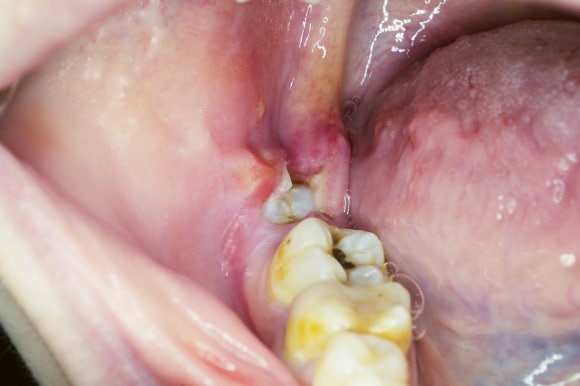

예시 사진

옆 어금니를 밀어내거나 위 예시 사진처럼 음식물이 끼어 염증이 생기고,

심하면 옆 치아의 신경까지 손상시키기도 합니다.

옆 어금니를 밀고 있는 사랑니 예시 사진

하지만 염증이 반복되거나

옆 어금니가 썩기 시작한다면

그때는 ‘빼야 하는 이유’가 분명해집니다.